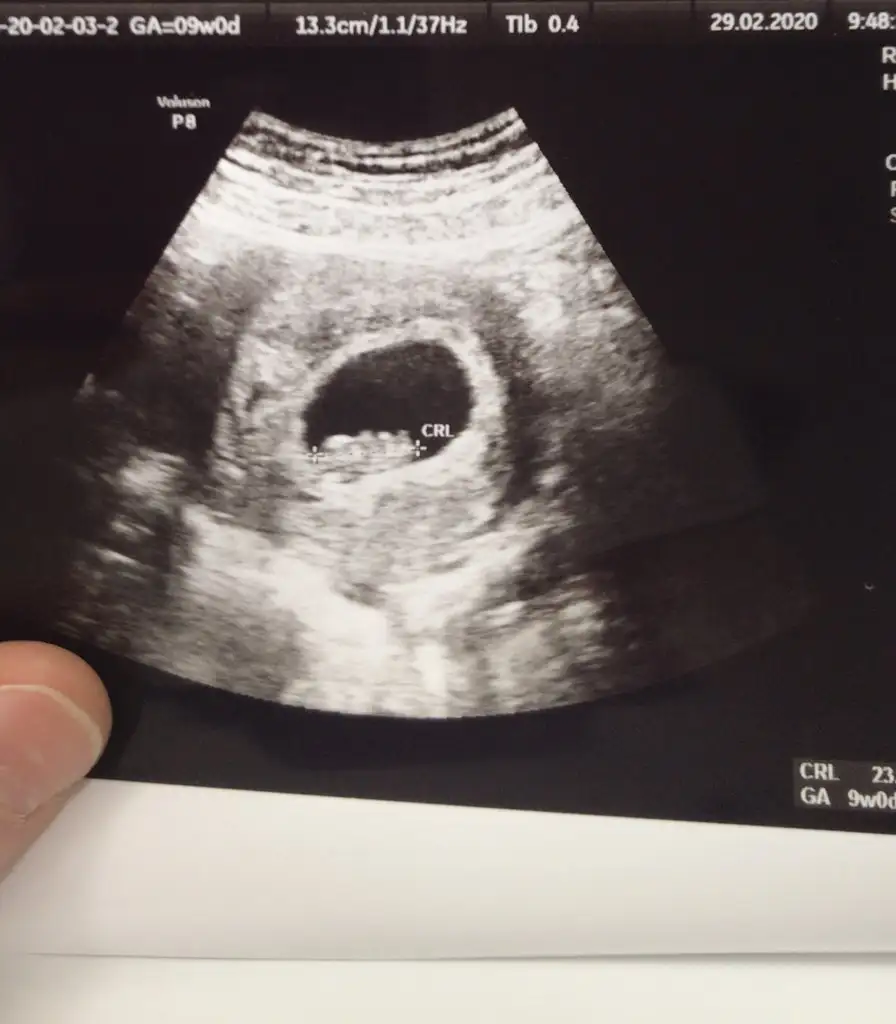

Ya kafam karisti bu fotografta. Telefonu saga cevirince farkli, sola cevirince farkli gorunuyor. Vajinal olunca tersini dusunuyoruz evet. Ama sizin kesenin durusunu anlayamadim. Yatay degil dikey duruyor kese. Daha dogrusu fotoyu oyle cekmis doktorunuz :)Vajinal olunca tersini mi düşünmek lazım anlamadım o kısmı. Bu vajinal

HahahYa kafam karisti bu fotografta. Telefonu saga cevirince farkli, sola cevirince farkli gorunuyor. Vajinal olunca tersini dusunuyoruz evet. Ama sizin kesenin durusunu anlayamadim. Yatay degil dikey duruyor kese. Daha dogrusu fotoyu oyle cekmis doktorunuz :)

Benim de bakınca kafam karıştı işin içinden çıkamadığım için siz de yorumlayın istedim ama sizin de kafanızı karıştırdım:))

Bi bakayım canım teşekkürlerRamzi Teorisi ve cinsiyet tahmini ( tutma olasılığı %85 miş )

Ramzi teorisine göre ( bilimsel bir araştırma sonucuymuş ve %85 doğruluğu varmış). İlk 6-8 haftalık ultrason görüntüsüne göre bebeğin kesenin içersinde soldan ya da sağdan girişine göre cinsiyet tahmini yapılıyor. Bilimsel olunca tecrübeli annelerimiz yada anne adaylarımızdan yardım istiyoruz...www.kadinlarkulubu.com

Belki burdan fikir alabilirsiniz